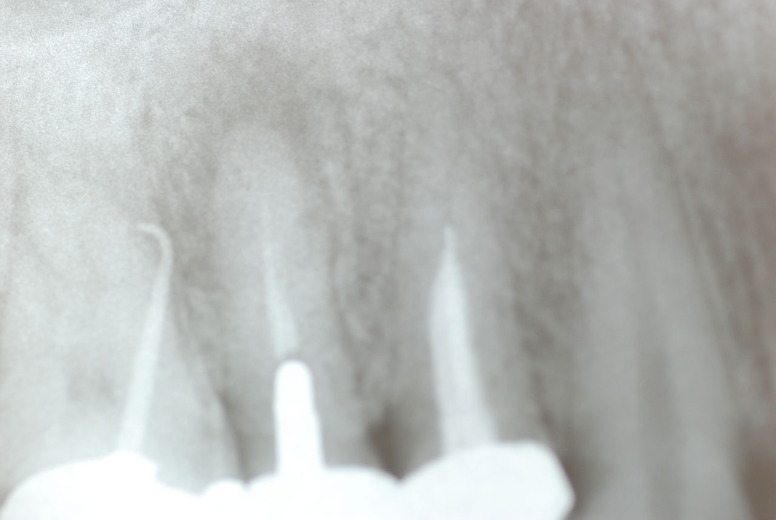

写真左下の親知らずが痛くなり抜歯しました。その後歯茎を除去して虫歯を露出させる処置を二回ほどしています。

レントゲンでは小さいですが、こう言う虫歯が一番怖いのです。

隣の14歳大臼歯がひどい虫歯になり治療不可能になりつつある状態のレントゲン